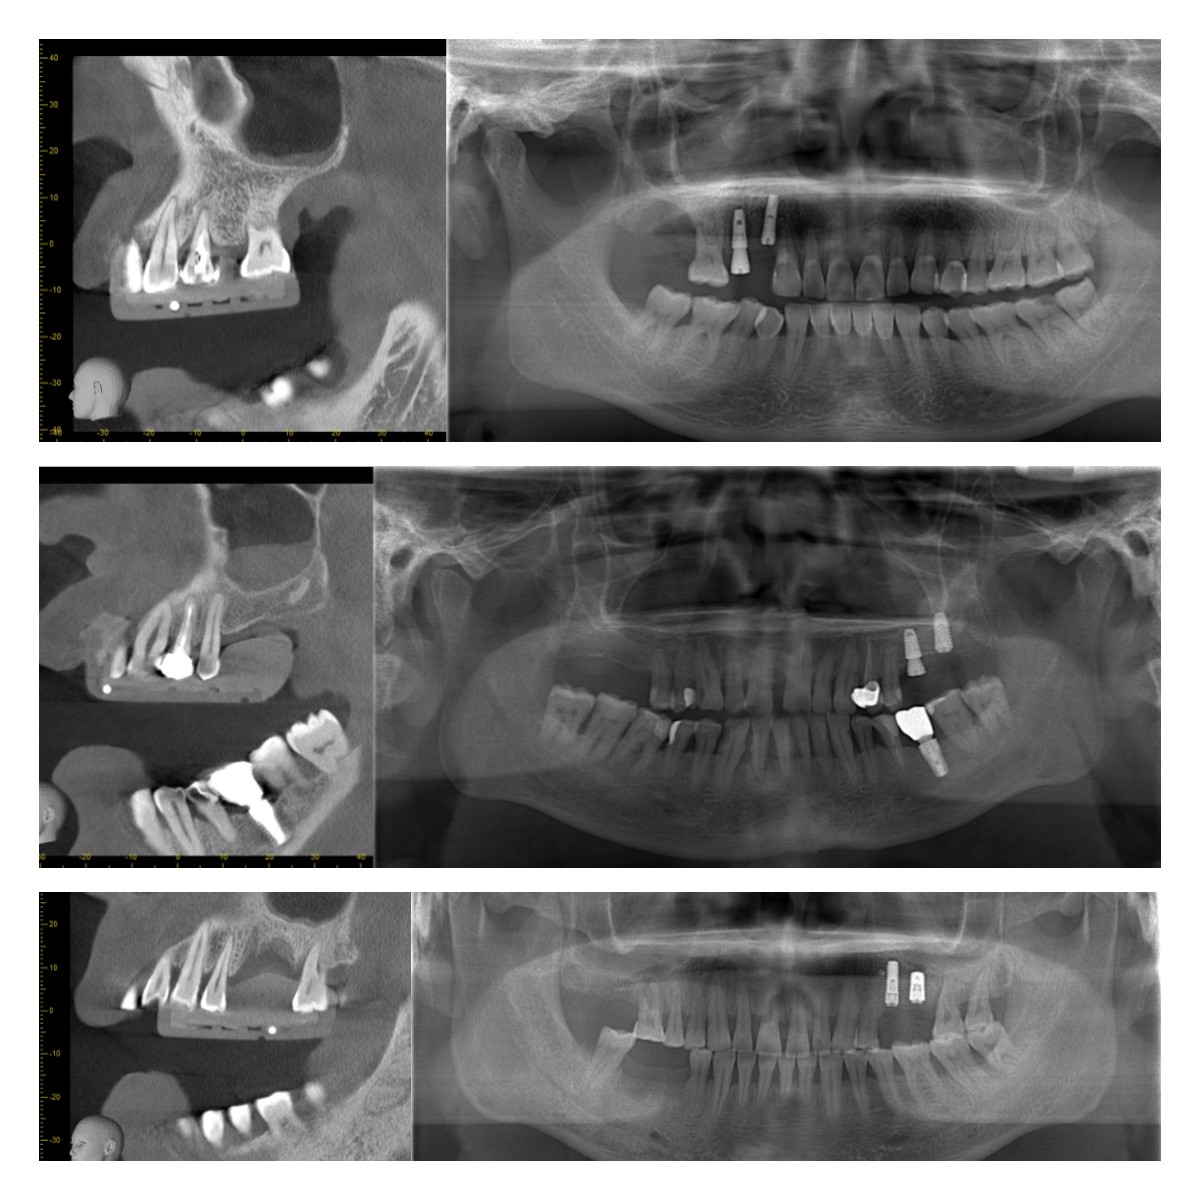

部分病例展示: